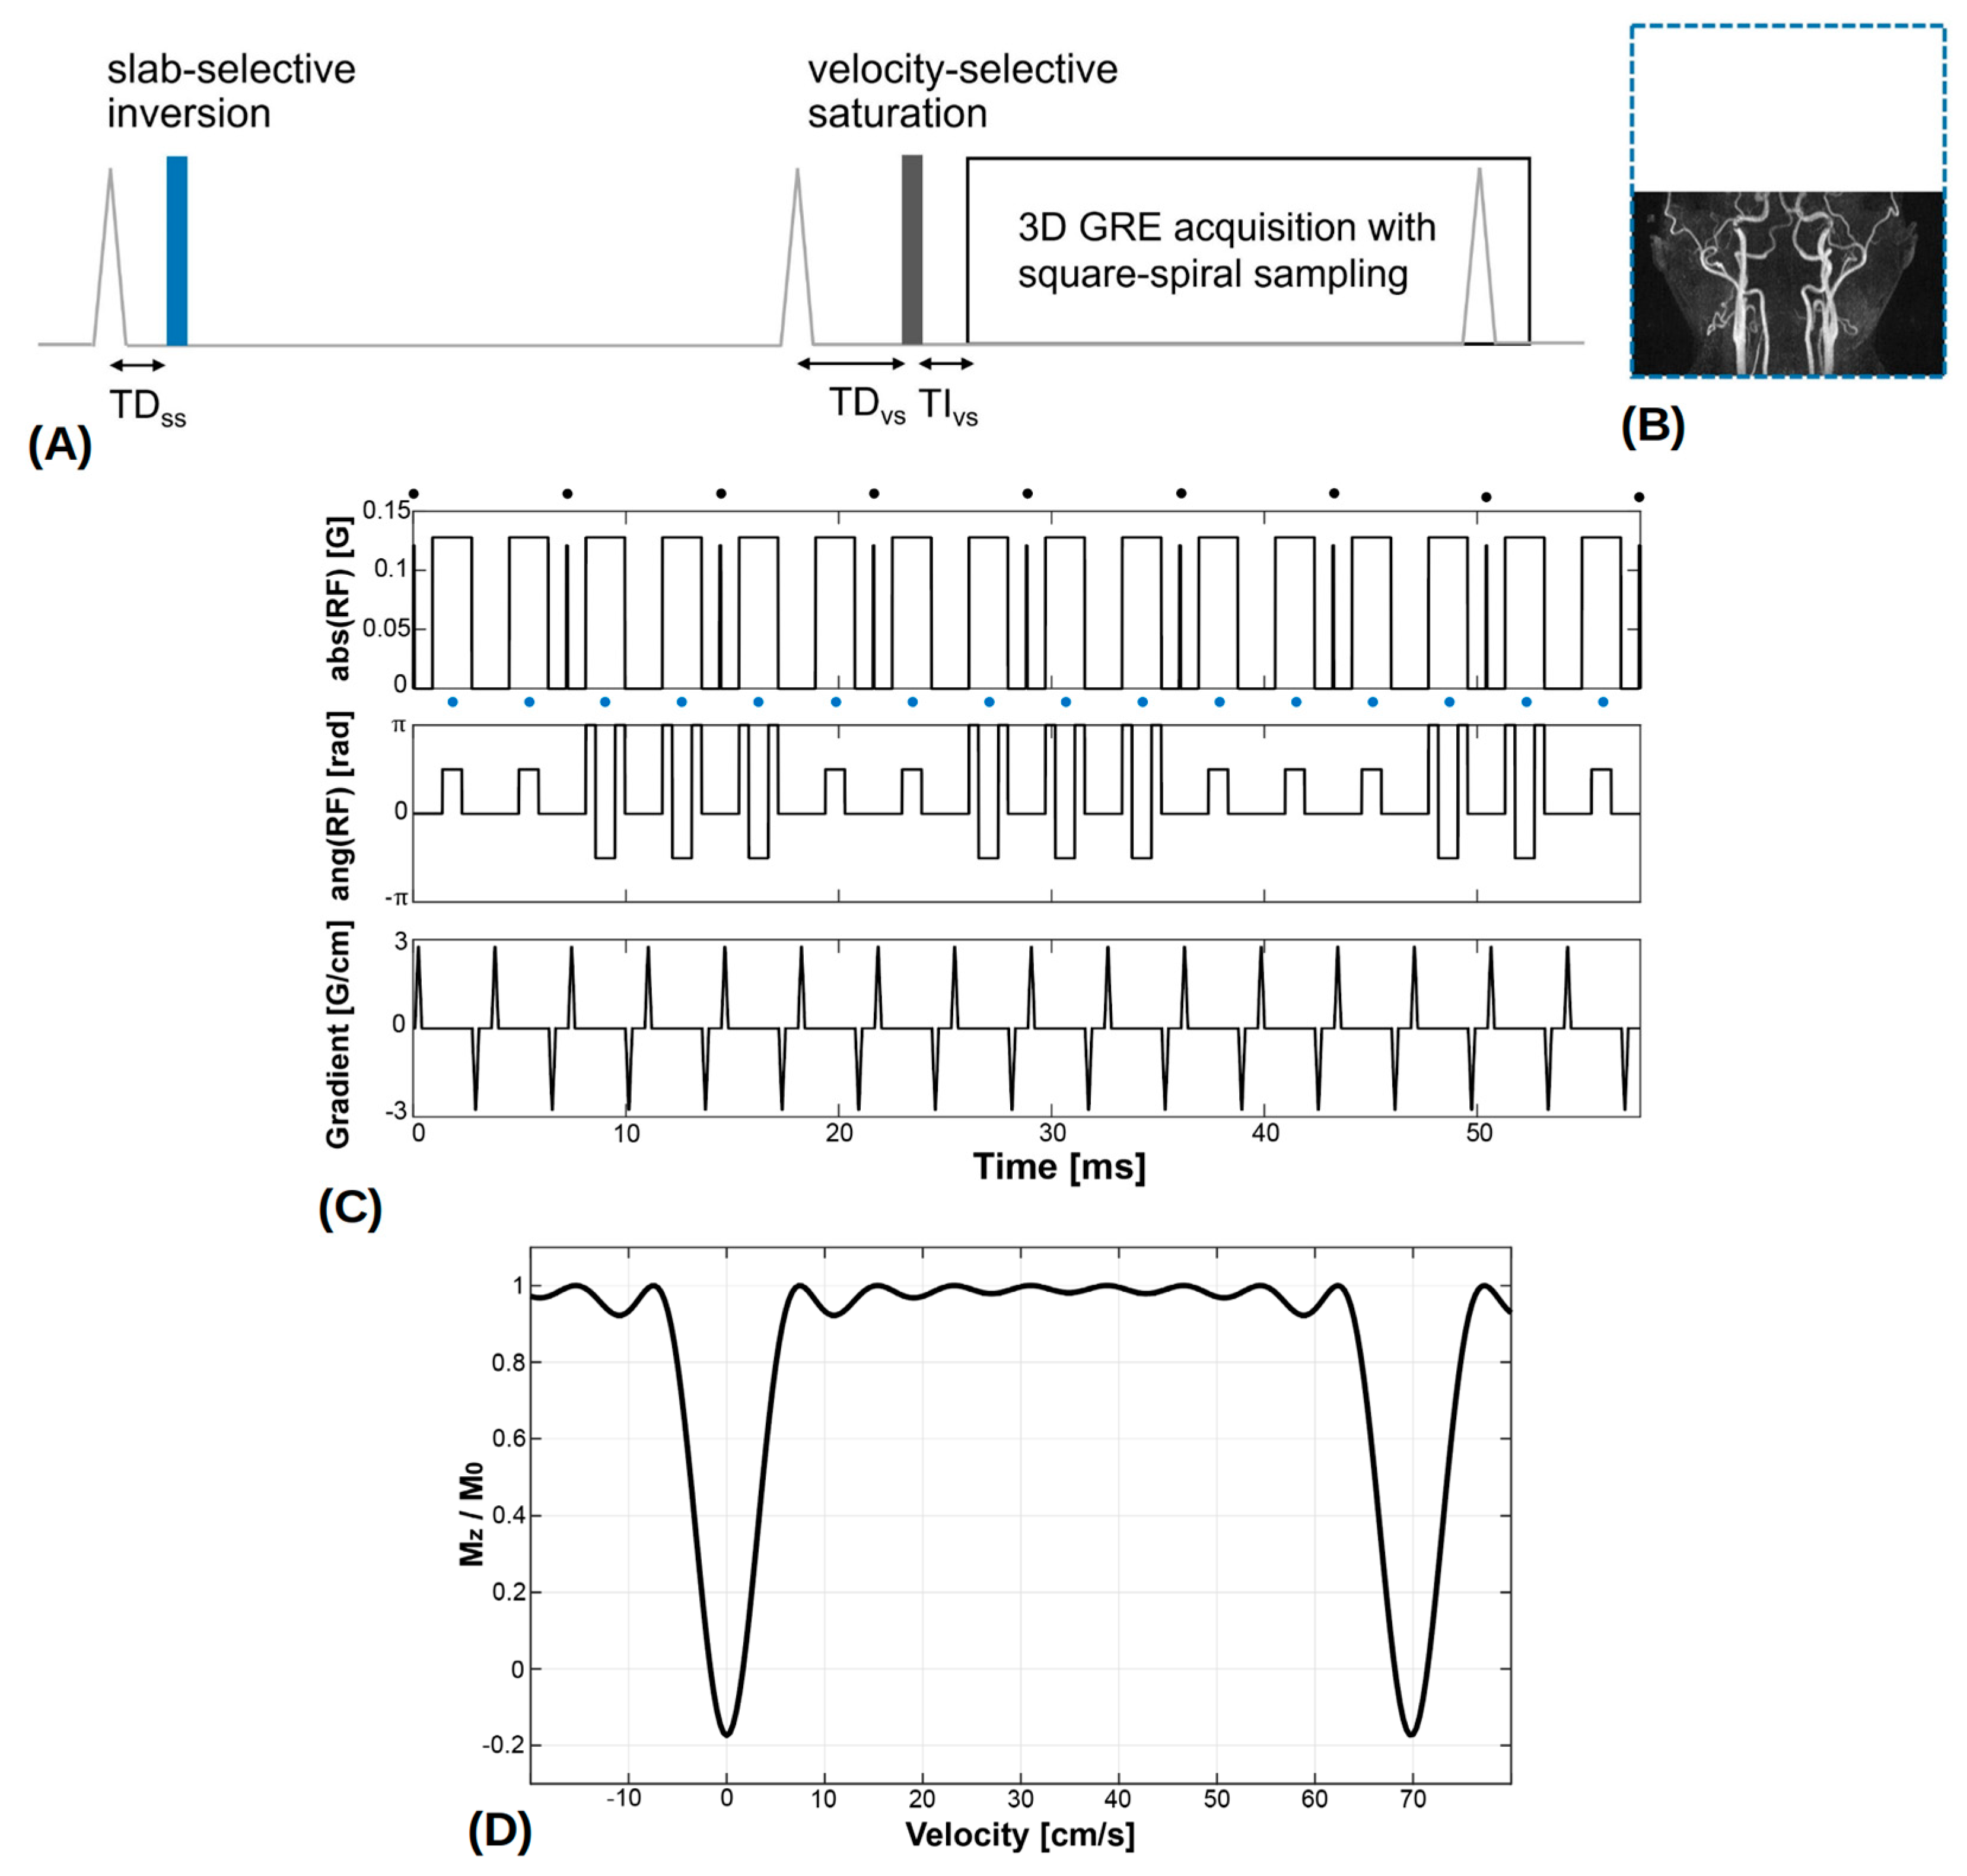

2.2. VS-MRA Pulse Sequence